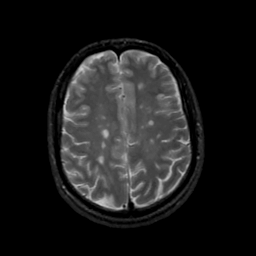

MR Study #20 October 6, 1991 -- Slice #36

[Home][Help][Clinical][Tour 1][Tour 2] Slice 36